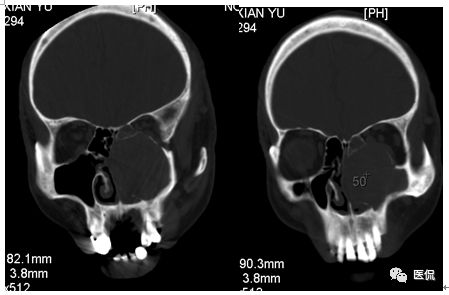

冠状位平扫

CT平扫及增强示:左侧上颌窦及鼻腔可见软组织密度影,呈膨胀性生长,周围骨质压迫性吸收破坏,累及左眶,病灶密度不均匀,周边区可见点状钙化,增动脉期轻度强化,局部见小灶性稍高密度区,静脉期病灶内见不均匀明显强化,CT值最高达117HU,延迟期强化范围有所增大。

本例病灶较大,周围骨质可见吸收破坏,并累及眼眶,病灶内少量钙化,增强扫描具有一定特征性,表现为动脉期轻度强化,局部见小灶性稍高密度区,静脉期病灶局部呈明显强化,CT值最高达117HU,延迟期强化范围有所增大,呈延迟渐进性强化的特点,推测为病灶内出血所致。